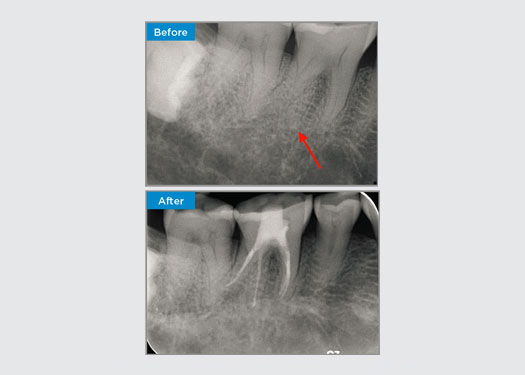

El paciente presentó pulpitis irreversible en la pieza dental 46. A partir de la radiografía preoperatoria, la pieza dental 46 se presenta con una raíz distal adicional (morfología dental Radix Entromolaris). Una escaneo CBCT ha confirmado la presencia de raíz distolingual con curvatura grave de la raíz. Una cuidadosa selección de limas es fundamental para esta raíz distobucal delicada.

Dr. Jack Lin, endodoncista, Sídney, NSW Australia

En esta situación, la preservación de la estructura del diente/raíz es esencial para reducir el riesgo de reborde, transporte, cierre, perforación y fractura de la raíz. La selección de casos, el diagnóstico y la planificación previa al tratamiento son importantes. La selección de limas de endodoncia con flexibilidad, eficiencia y respeto por la anatomía de la raíz natural es fundamental.